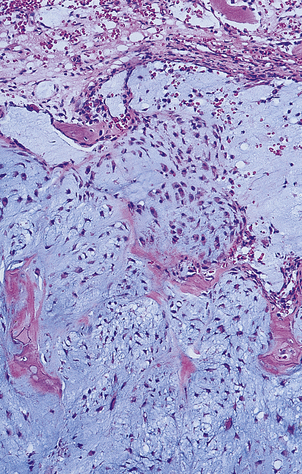

Chondrosarcomas, in contrast to osteosarcomas, grow slowly and arise not only in long bones but also in the pelvis, ribs and spine (Fig. 25.14). These tumours may be well differentiated and can resemble normal cartilage. Surgical excision is the treatment of choice, as radiotherapy and chemotherapy are usually ineffective.

image

Fig. 25.14 Chondrosarcoma. The tumour has arisen in a pelvic bone of a 42-year-old female. Histologically the abnormal cartilage is much more cellular than normal.